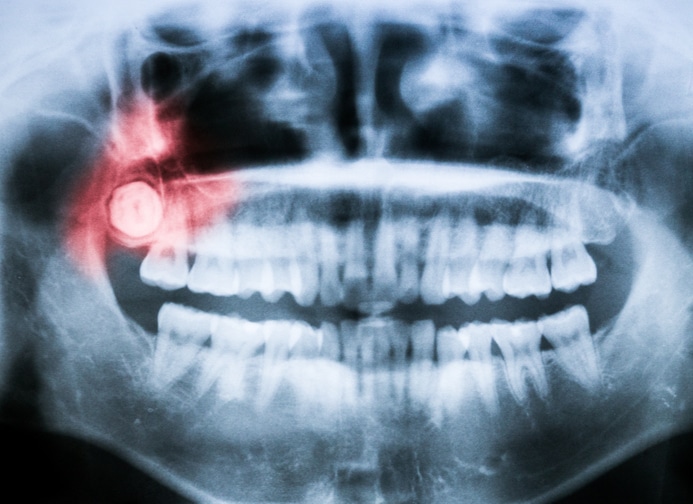

Of course, “not bothering you” must be put into context Dr. Farmer-Dixon cautions. It’s possible, she explained during a recent interview with BlackDoctor.org (below), “They could not be bothering you, but because of how they’re positioned over time they could have bone resorption and cause problems down the road.” Dental x-rays are the only way to know what’s really going on with your wisdom teeth.

If your jaw isn’t large enough, the wisdom teeth can become impacted, which results in one of two things. One, they are either unable to fully form, or two, they become misaligned. In this case, having your wisdom teeth pulled will ensure all your teeth sit well in your jaw.